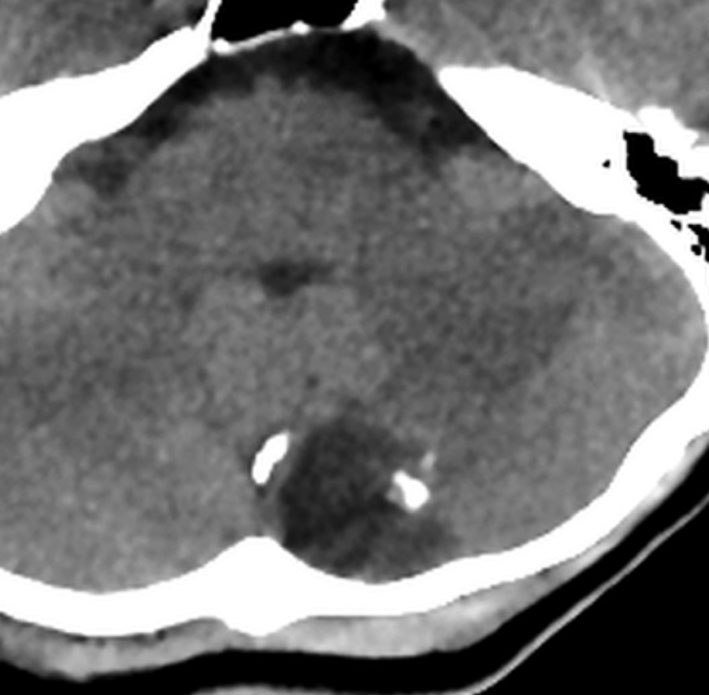

頭痛と嘔吐という髄膜刺激症状で発症しました。鞍結節部の類皮のう胞が破れたものです。黄色い矢印の先の白い点々にみえるのが散らばった内容物です。油滴です。